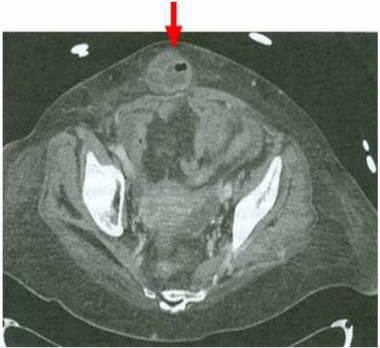

27.68歲女性因肚臍周圍疼痛合併噁心嘔吐至急診,理學檢查發現體溫37.5℃,且肚臍周圍有壓疼,血液檢查WBC:14500/µL, 分類segment:85%,腹部電腦斷層結果如圖,最可能的診斷為何?

(A)acute appendicitis (B)ventral hernia (C)acute diverticulitis (D)adynamic ileus